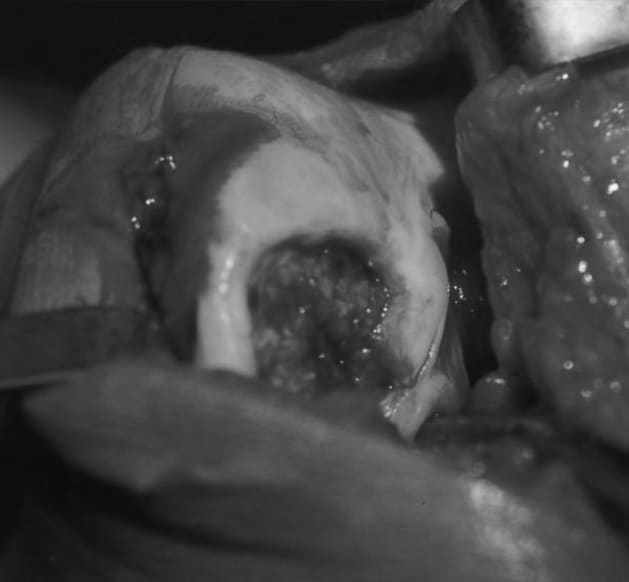

Situs intraoperativ

Vor Entfernung des nekrotischen Gewebes sowie vor Anfrischen und Anbohren.